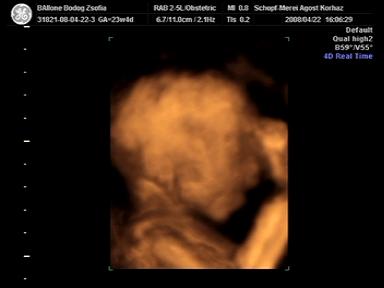

na, megvolt a 4D ultrahangunk tegnap! nagyon klassz volt, ugye abban megegyezhetünk, hogy szinte minden nap nézegetnénk a babánkat, babáinkat, szóval tényleg hatalmas élmény!

mindjárt teszek fel képeket is ;)

amúgy a bébi olyan 730 g körül van most, de ami a fura, hogy mostanában sosem mér hosszúságot! azt mondta a néni, hogy ilyenkor kb. 3-4 cm a talpa! :) annyira édes! tényleg olyan kis manócska!

a lelet grav.s. 24-et határoz meg, BPD 60mm, OFD 76mm, AC 198mm, és végül FL 46mm. sosem tudom, hogy mik ezek a betűk, de mindjárt utánanézek! ;)

szóval akkor a képecskék!

Kép Benedek 23 hetesen és 4 naposan Kép Benedek ásítás közben Kép és az igai bizonyíték, hogy kisfiú